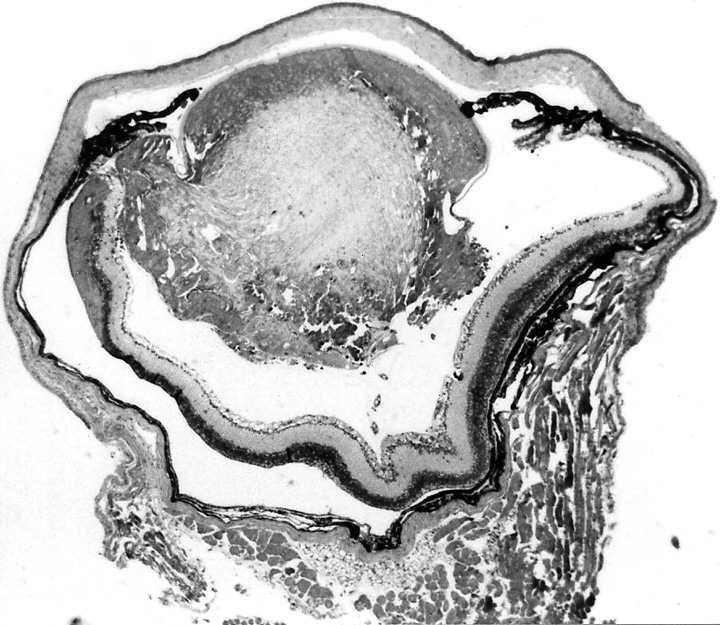

Figure 1c. Eye of To3/To3 homozygote, age 69 days.

The lens capsule has ruptured, and lens material has leaked into the abnormally small vitreous chamber.